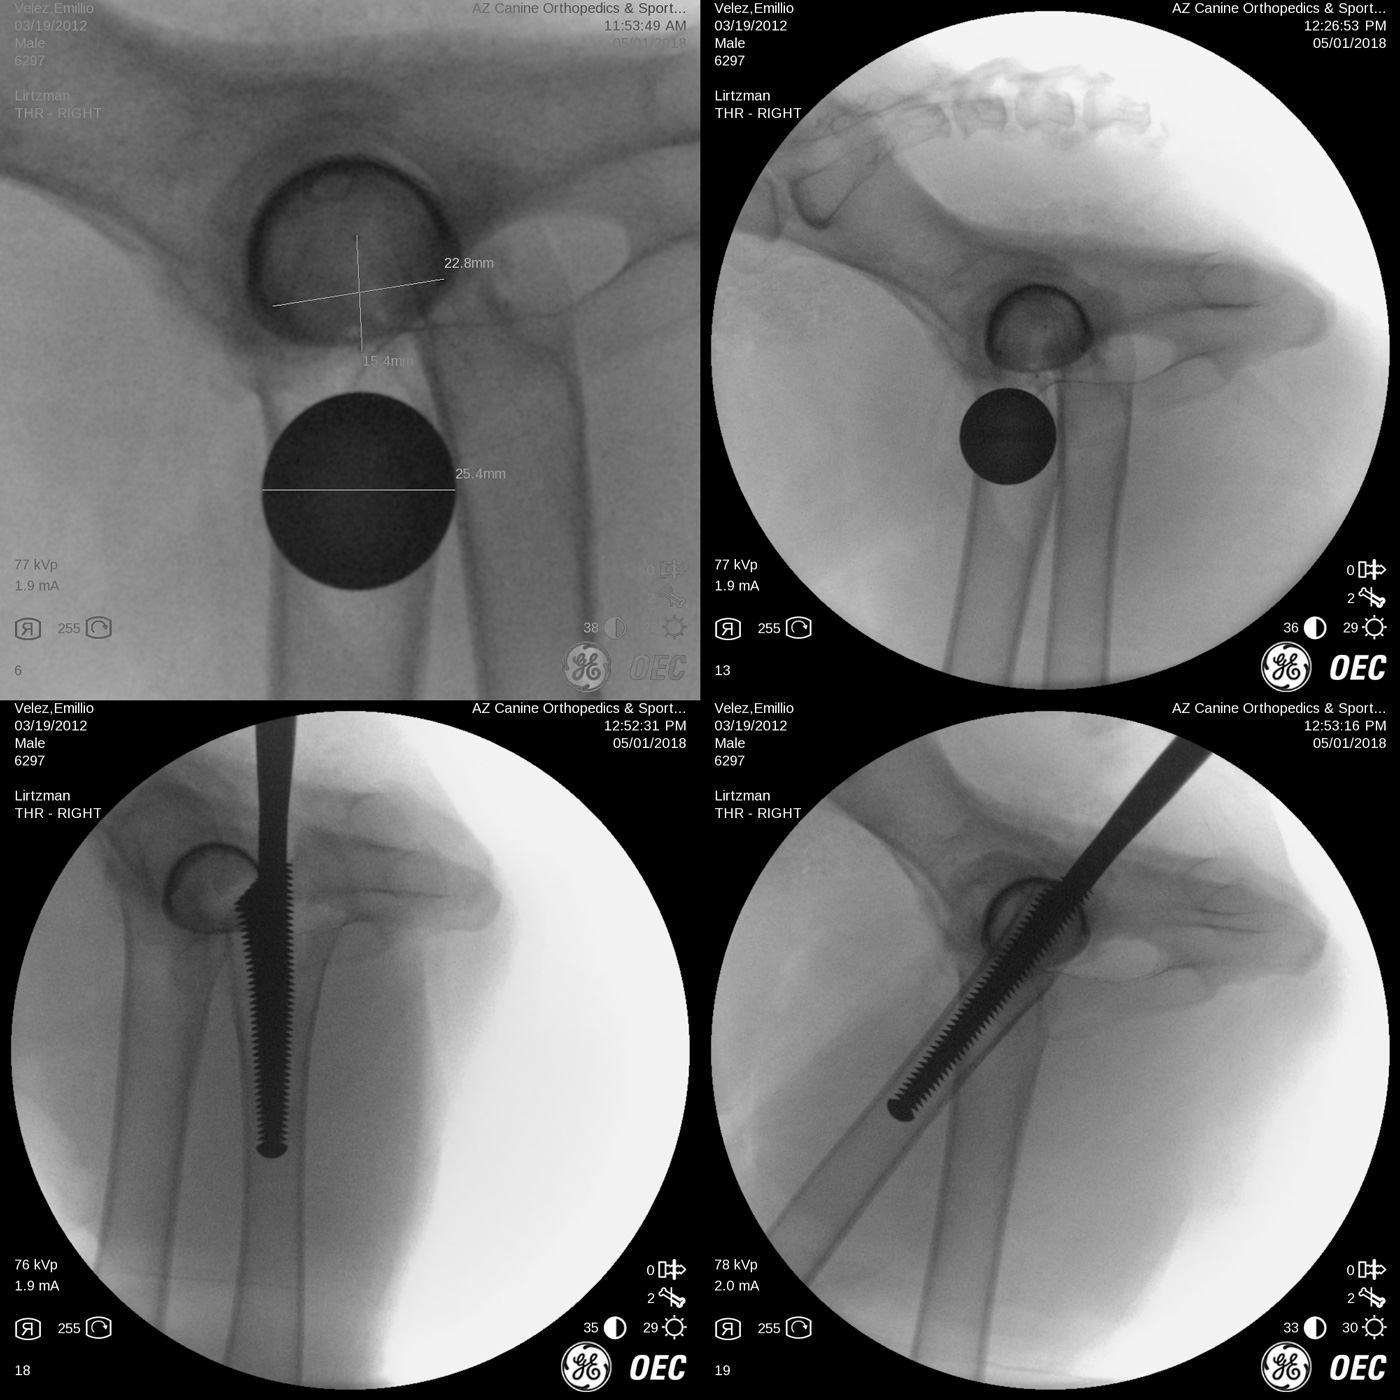

Risk associated with patient malpositioning or movement of the pelvis during surgery, bone preparation techniques, implant sizing and implant postion-orientation have been greatly reduced by the addition of intra-operative x-ray imaging as seen below. The most common and significant problems include: